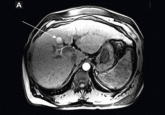

ArticleHepatocellular carcinoma: Options for diagnosing and managing a deadly diseaseAuthor:Federico Aucejo, MDPublish date: October 1, 2013Because early diagnosis improves the chances of survival, it is important to identify patients who would benefit from surveillance.Read More